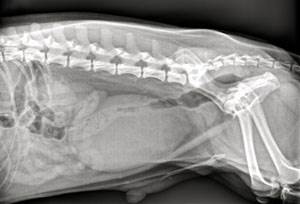

На приеме врач осматривает пациента, собирает данные о перенесенных заболеваниях, проведенной терапии. При пальпации брюшной полости выявляется перерастянутый атоничный мочевой пузырь. Далее проводится подробный неврологический осмотр, проверяются рефлексы. Это позволяет определить степень неврологического дефицита, локализацию первичной проблемы (например, выясняется, какой сегмент спинного мозга оказался поврежден).

Дальнейший поиск повреждений позвоночника, спинного мозга включает в себя рентгенографию, миелографию, КТ и МРТ.